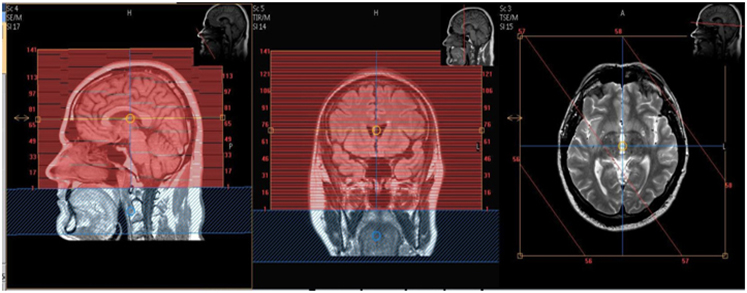

No angles.

Cover the entire nose.

Cover below skull base to at least 1 cm above Vertex.

Include additional air on top of scan for slice wrap.

| AXIAL pre (run only if requested) | 3D T1 FFE | 3D GRE | 1.3 mm | 0mm | None | 25cm | No angles. INCLUDE ADDITIONAL AIR ON TOP OF SCAN FOR SLICE WRAP |

| AXIAL | 3D T1 FFE | 3D GRE | 1.3 mm | 0mm | None | 25cm | No angles. INCLUDE ADDITIONAL AIR ON TOP OF SCAN FOR SLICE WRAP |

| AXIAL | T2 VISTA | TSE | 1.3mm | 0mm | None | 25cm | No angles. INCLUDE ADDITIONAL AIR ON TOP OF SCAN FOR SLICE WRAP |